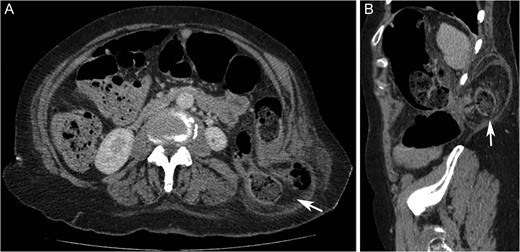

On examination, there was a 15 cm, irreducible, mildly tender lump in the left superior lumbar triangle, in the region of previous lipoma excision. There were audible bowel sounds on auscultation of the lump. No other swellings of the abdominal wall were identified and the patient was not known to have any hernias. Abdominal radiograph revealed faecal loading in the ascending colon with dilated large bowel loops (Fig. 2). Subsequent computed tomography (CT) scan showed a left superior lumbar triangle hernia containing a loop of colon (Fig. 3) with dilated large bowel proximal to this, in keeping with obstruction.

Computed tomography axial (A) and sagittal (B) images showing left sided superior lumbar triangle (Grynfeltt-Lesshaft) hernia containing loop of (‘arrows’) in a 72-year-old woman.